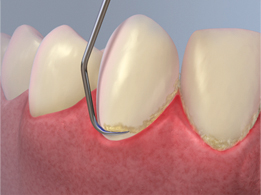

Dental scaling occurs with manual hand instruments, ultrasonic instruments or both. The dentist will start the procedure with a thorough examination of your mouth. Next, an ultrasonic scaling device will be used to eliminate the plaque bacteria with sonic vibrations. The ultrasonic scaling device removes tartar (calculus), plaque and biofilm from the tooth surface and underneath the gum line. A manual instrument may be used next to remove the remainder.

Root planing involves detailed scaling of the root surface to decrease inflammation of the gum tissue. The dentist scales the root surface to smooth out rough target areas, eliminating plaque and bio-film development.